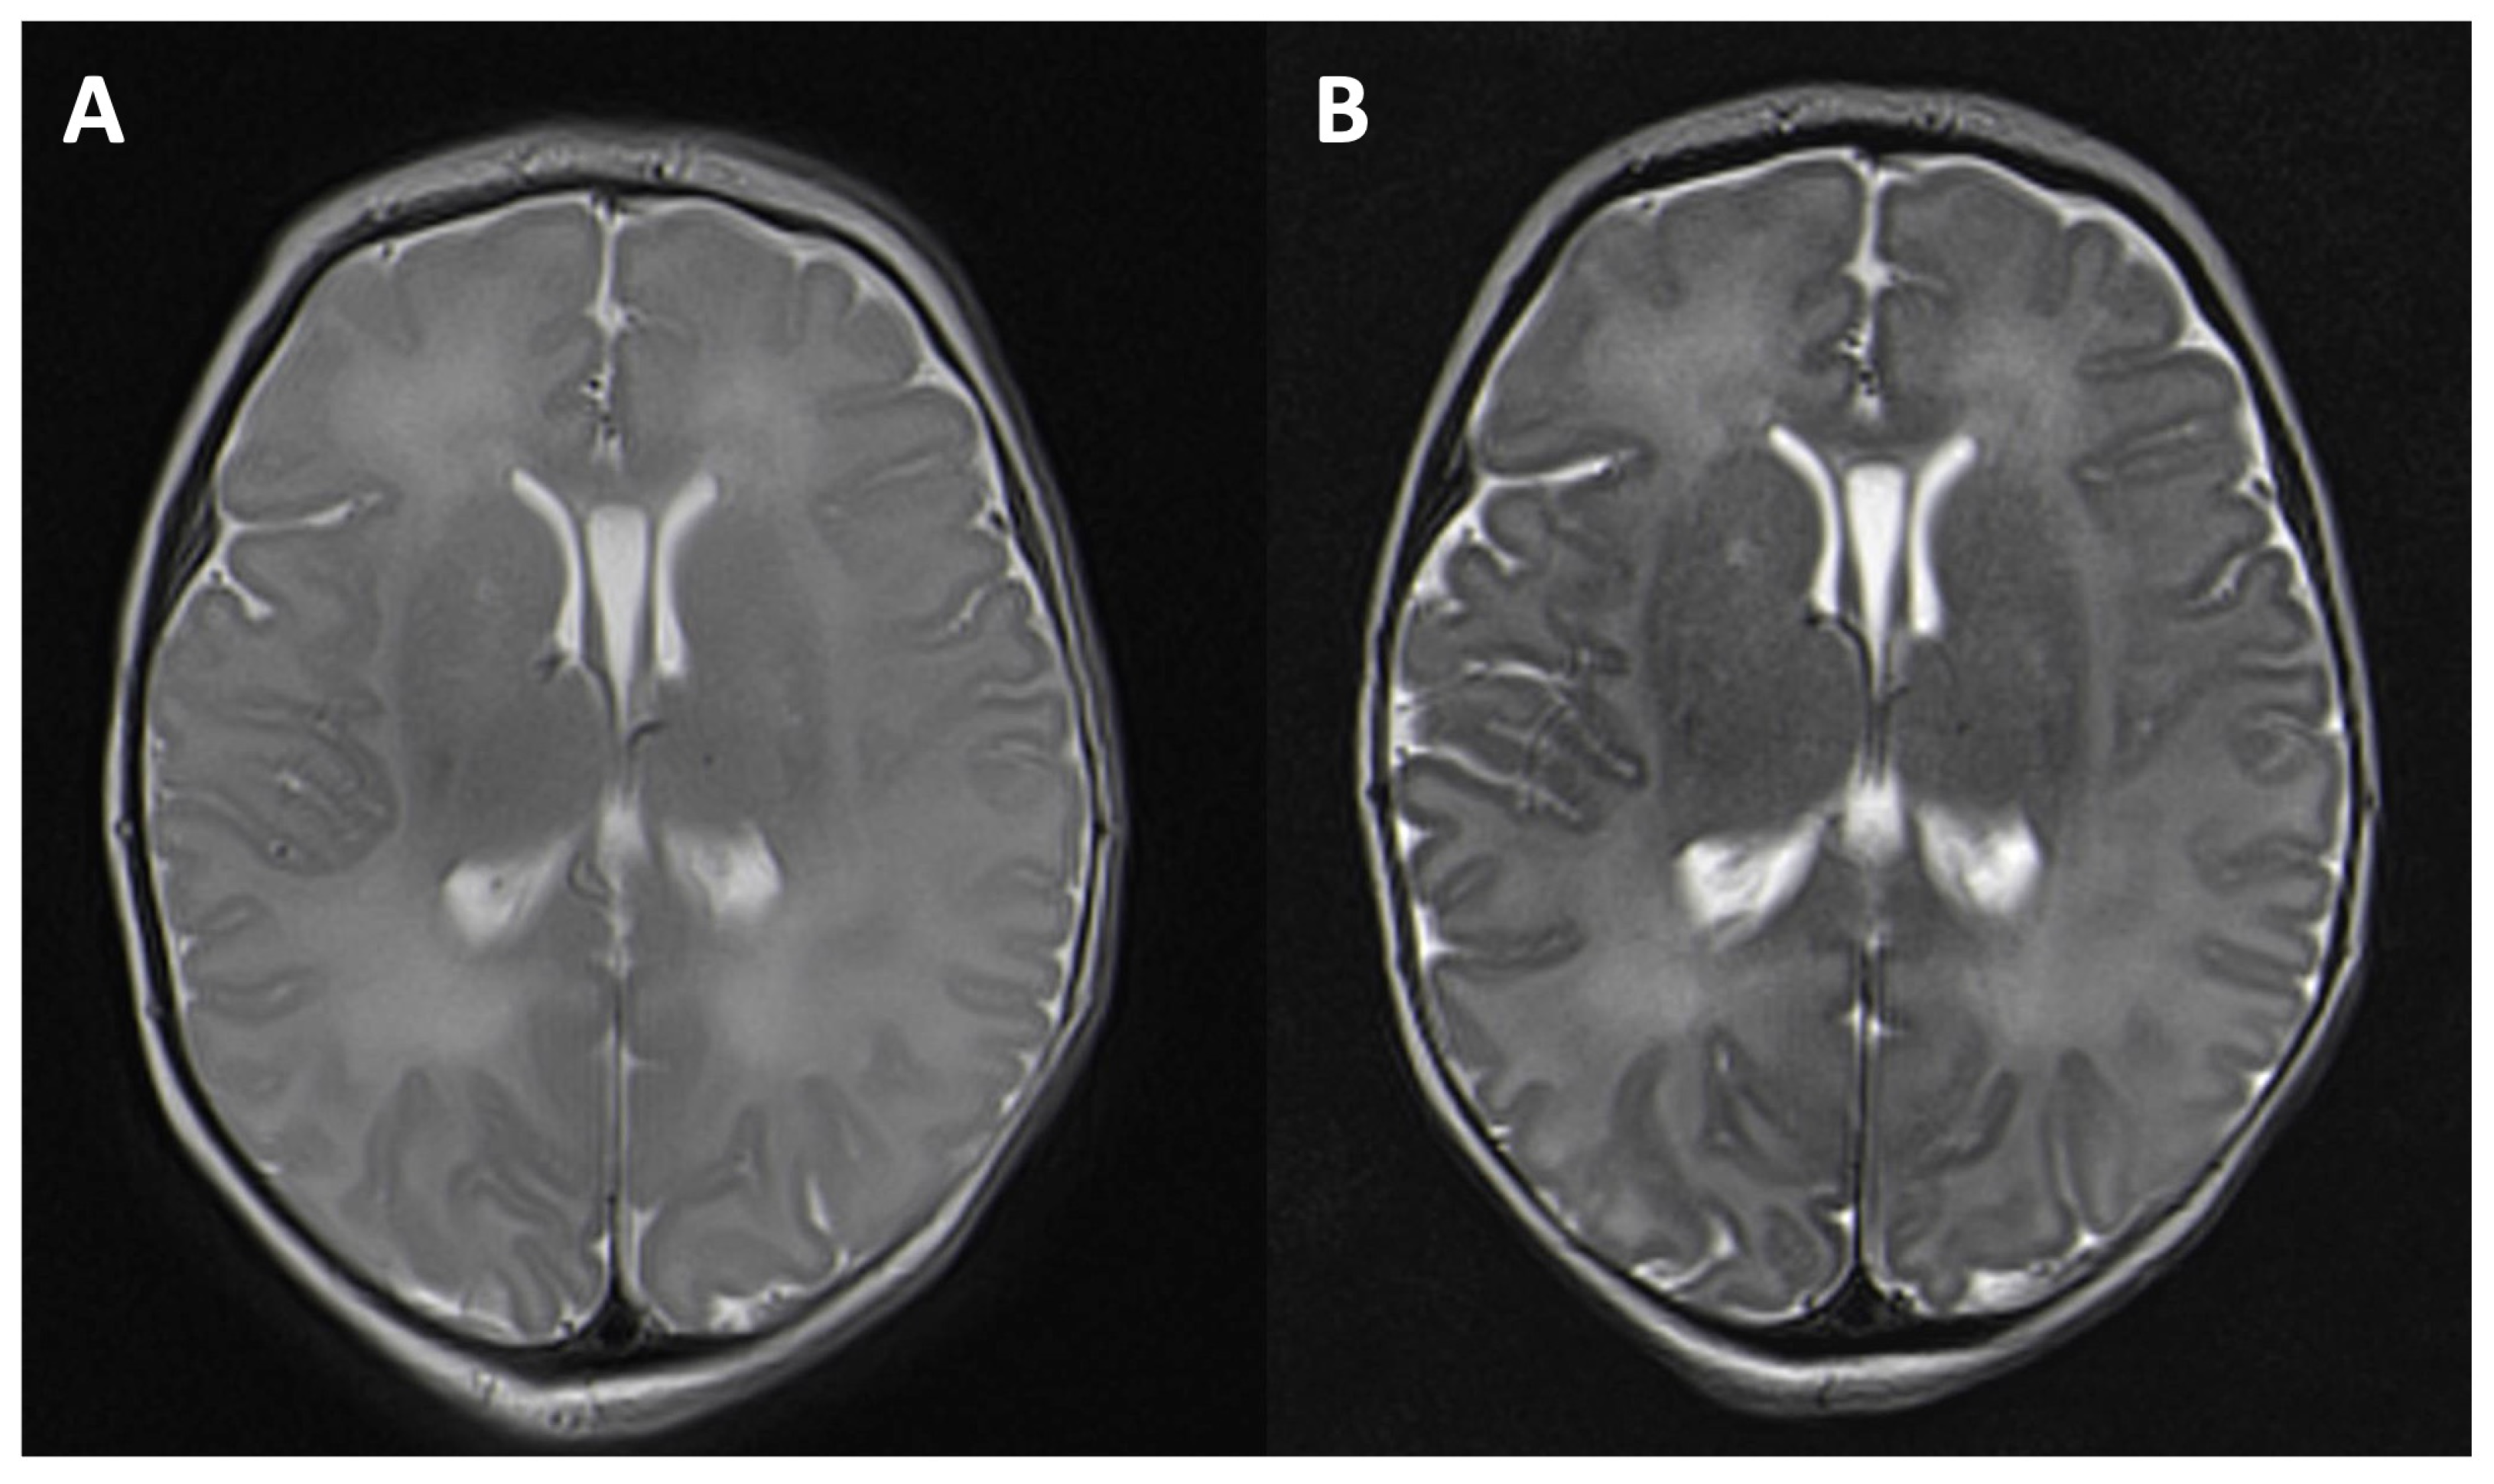

| 0–6 | 47 | 0.11 | 0.18 | −0.10 | −0.07 | <0.001 (*) |